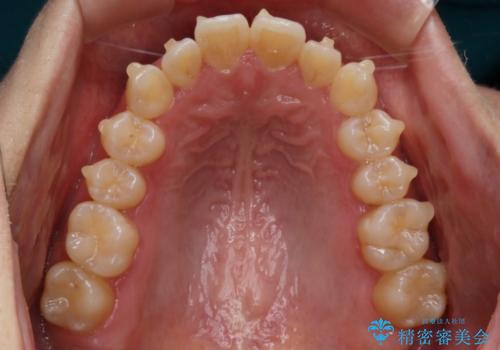

【非抜歯】部分矯正でも治る 前歯の反対咬合

- 前歯にガタつきを主訴にご来院されました。

奥歯の嚙み合わせに問題がほとんどみられなかったため、インビザライン ライトパッケージでの部分矯正を行うこととなりました。

今回のケースでは奥歯の噛み合わせに問題がほぼみられなかったため、前歯の位置のみに焦点を当て部分矯正を行いました。

適応されるケースが限られるものの、適応であった場合の治療期間は全体矯正と比べると格段に短くなり、費用も抑えられます。